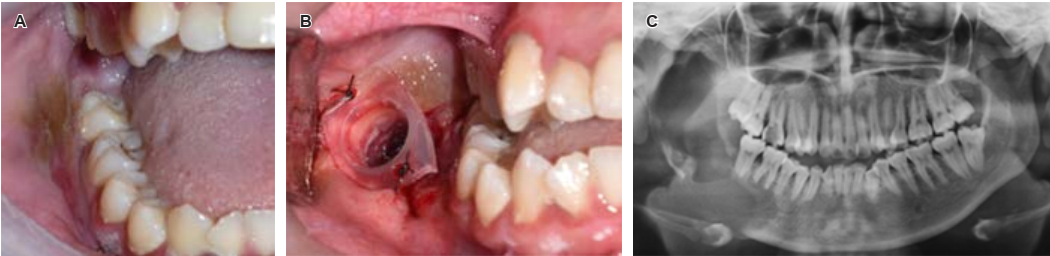

Bajo anestesia local, se llevó a cabo punción exploratoria sin obtención de muestra representativa, por lo que se realizó biopsia incisional y extracción de órgano dental relacionado y arrojó como resultado ameloblastoma uniquístico de tipo mural con patrón plexiforme. Debido al tamaño de la lesión, edad y posibilidad de apego por parte del paciente a sus citas, se opta por un tratamiento conservador, el cual consistió en la colocación de un tutor bajo anestesia local en el borde anterior de la rama mandibular derecha para realizar descompresión de la lesión, se realizó un seguimiento clínico e imagenológico durante dos años en los que se logró la remodelación completa del cuello del cóndilo, rama, ángulo mandibular y la parte anterior del cuerpo mandibular del lado derecho, permaneciendo únicamente una lesión en la zona retromolar de aproximadamente 4 × 3 × 5 cm, por lo que se decide realizar enucleación y curetaje (Figuras 2 y 3), el tejido obtenido se mandó en su totalidad a estudio histopatológico, con el cual se obtiene el diagnóstico de ameloblastoma uniquístico de tipo mural plexiforme, se presentan controles de la paciente clínicos e imagenológicos un año después de la enucleación, se planea mantener un control clínico a largo plazo (Figura 4).

Figura 2 Biopsia incisional. A) Fotografía inicial para colocación de tutor. B) Fotografía con el tutor fijo a mucosa oral. C) Ortopantomografía de control postquirúrgica.